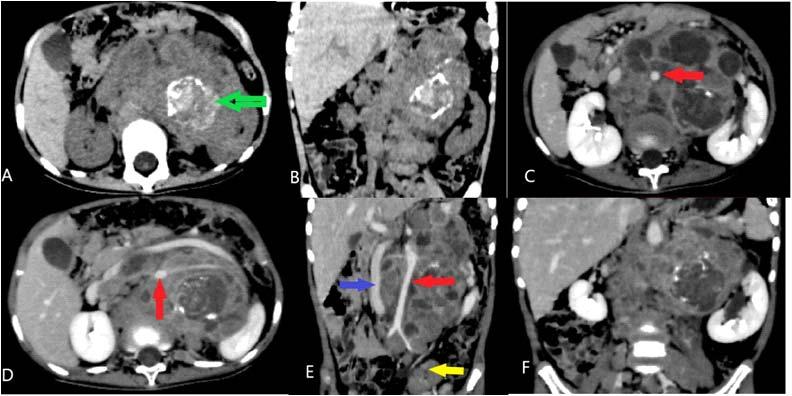

Among the metabolically abnormal patient’s population 20% (n=3) had Hypoglycemia, 40%(n=6) presented with Dyselectrolytemia, 26.67% (n=4) had Uremia, 13.33% (n=2) presented with Hepatic encephalopathy. Overall, 31 patients underwent Lumber puncture, of which CSF report shows abnormality in 11 (35.48%) cases and normal in 20 patients (64.51%). Abnormal CSF report suggesting viral meningoencephalitis found in 46% (n=5), bacterial meningitis in18% (n=2), Tuberculous Meningitis in 27% (n=3), Aseptic meningitis in 9% (n= 1). All 65 subjects underwent CT scan brain among which MRI Brain also done in 55 cases. CT findings is normal in 44.62% (n=29), abnormal in 55.38% (n=36). The most common CNS lesion on CT scan was infarction in 10.77% followed by ring lesion in 9.23% and intracerebral Hemorrhage in 7.96%. We observed cerebral infarction is causative factor of Seizure in female (15%) but intracerebral hemorrhage and ring lesion are most common findings in male, comprising 11.11% patients at each category. The CT scan in new onset Seizure of elderly patient population revealed Infarction in 28.57%, Gliosis in 19.04% and cerebral atrophy in 14.28%. The breakup of findings in MRI Scan of 55 patients shows Hyperintensities on T2, indicating Demyelination / Inflammation/edema in12.31% followed by infarction in 10.77% and ring lesion in 9.23%. In the female population, hyperintensities on T2 MRI found in 15% and Infarction in 15% whereas among the males intracerebral Hemorrhage, Ring lesion and hyperintensities on T2 found at similar occurrence rate @11% in each of these three types of lesions. EEG was done on 80% patients (n=52) of whom 22 patients has abnormal discharge in EEG but 30 patients have normal presentation. Among 65 patients one female expired due to Acute Demyelinated Encephalomyelitis (ADEM) and two males expired one due to Hemorrhage, another one with CNS infection when undergoing treatment indoor.

We found a strong positive correlation between abnormal EEG and abnormal Neuroimaging with Correlation coefficient of 0.902, (P- Value 0.0138) but almost no correlation found between normal EEG with normal Neuroimaging (Figs 1-4).

About 23% of patients with adult onset first seizure has metabolic derangement and the most common etiology was Dyselectrolytemia. The most common Central Nervous System (CNS) Infection as detected by CSF study was viral meningoencephalitis followed by Tuberculous Meningitis. The most common CNS lesion detected by CT studies as well as by MRI Brain was infarction and ring lesion, the two Neuroimaging studies corroborated in 75.38% of Seizure patients. Abnormal discharge in EEG found in34% cases. In majority patients EEG report was normal. EEG abnormality was more common in patients with Focal Seizure rather than GTCS patients. Thus, the most common etiology of first Seizure onset at adult age over 18 years were metabolic derangements (16.92%), CNS Infection or Inflammation (15.38%) and intracerebral Space occupying lesion (15.38%), usually ring lesion, tumors and Metastasis. Idiopathic Seizure found in 7.69% patients. The Correlation between abnormal Neuroimaging and abnormal EEG is strongly positive and statistically significant (P -Value = 0.013) but the same is not true in cases of normal Neuroimaging and normal EEG findings.